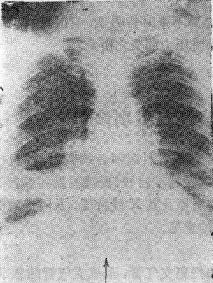

第一节 肺不张的发生机制、分类及病因一、肺不长的发生机制 要保持肺气腔处于良好膨胀状态,必须具备三个基本的条件。 (一)气道必须保持通畅 如果气管是某一部分发生阻塞则引起远侧的肺组织萎陷,气体被吸收。这种肺不张发生是以支气管梗阻为直接的原因,诊断的基本问题是找出支气管梗阻的原因,这类肺不张是指狭义的肺不张。 (二)胸腔负压的存在 如果胸腔内的负压消失则肺被压缩将导致压缩性肺不张,这类我们通常称之为肺压缩(压缩性肺不张)。 (三)肺组织必须具有良好的弹性各种疾病导致的肺纤维化,均可引起肺组织弹性减低,致肺组织萎陷。 另外,近代文献中所提到的所谓“圆形肺不张”(roundatelectasis),是肺基底胸膜附近周围肺叶的萎陷,其重要的X线特征是“彗星尾征”-肺血管。 二、肺不张的分类 肺不张的分类方法甚多,从肺脏的解剖和X线形态可分为七类。 (一)一侧性全肺不张主支气管梗阻或全肺破坏、纤维化-肺硬变。 (二)大叶性肺不张 叶支气管梗阻为主。 (三)肺段性肺不张 段支气管的梗阻。 肺癌、结核、炎症是造成支气管梗阻的主要原因,也是上述三种肺不张的直接原因。 (四)小叶性肺不张 多见于支气管肺炎和支气管哮喘的患者。 (五)线状或盘状肺不张 多见于膈肌升高的患者,如肝脏增大、腹水等。 (六)压缩性肺不张 由气胸、胸腔积液、巨大胸壁或纵隔肿瘤、巨型肺囊肿,肺大泡等引起。 (七)弥漫性肺不张(限制性肺不张)各种原因所致弥漫性肺间质纤维化。 三、肺不张的致病原因 导致肺不张的病因是很多的,现分类叙述如下。 (一)支气管梗阻(图115-1、2) 1.支气管腔内梗阻 如肿瘤、粘液栓、支气管狭窄、支气管异物、支气管断裂、支气管痉挛等。 2.支气管腔外压性梗阻 如淋巴结肿大、血管环压等图115-1右下肺不张

图115-1 右下肺不张